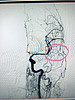

– Через введенный проводник в сосуды вводился специальный клеевой материал - эмболизат, который «заклеивал» АВМ и сосуды, которые ее питали. На каждом этапе благодаря введению контраста, мы видели на экране монитора, как АВМ уменьшается в размерах, пока она полностью не исчезла, - рассказал врач-рентгенхирург.

Операция длилась более 4 часов. Специалистам удалось выполнить тотальную эмболизацию АВМ. Прямо с операционного стола пациентка была направлена на контрольную компьютерную томографию. Исследование подтвердило отсутствие каких-либо кровоизлияний или ишемических изменений. Благодаря тому, что специалисты полностью «выключили» АВМ из кровотока пациентка больше не нуждается ни в каких вмешательствах по поводу этой патологии. После пробуждения от наркоза, пациентка была обследована на предмет неврологической симптоматики – никаких жалоб она не предъявляла, речь у нее восстановилась. На сегодняшний день кировчанка выписана домой.